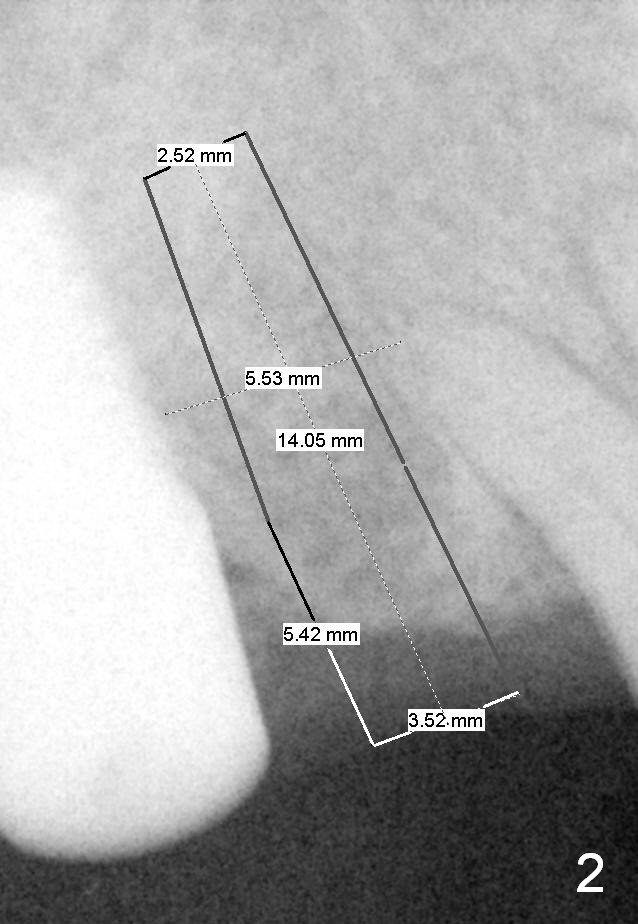

The implant at the site of #3 is intentionally placed distal as part of a plan to distalize the teeth #4-6 (Fig.1). Ortho started, but the patient did not want to pursue it. The most efficient way to terminate it is to dislodge every one of brackets/bands. When it is time for restoration for implants at the sites of #3 and 30, it is a challenge to deal with the space mesial to #3. The patient is planning to leave the country in 20 days. Fortunately he agrees to have an extra implant (Fig.2). It must be small in diameter. The initial osteotomy does not go on smoothly, approaching the apex of the tooth #4 (Fig.3 A). The osteotomy is moved distally and the trajectory is changed. It appears to be overcorrected (Fig.4). After re-adjustment, a 3.5x14 mm implant is placed with insertion torque between 15 and 20 Ncm (Fig.5). An abutment is placed with perio dressing applied around it as well as #3 after suturing. When the wound heals and before the patient leaves the country, the abutment is removed.